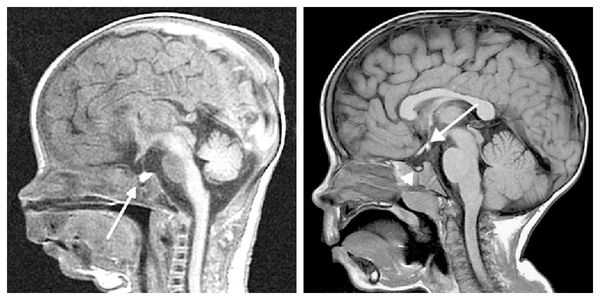

- Лучевая диагностика.КТ головного мозга с контрастированием является основным методом диагностики, позволяющим определить участки геморрагии, некротические ткани, объемные образования любого размера. Магнитно-резонансная томография мозга или рентгенография черепа в боковой проекции выполняются при отсутствии возможности проведения КТ. Рентгенография позволяет обнаружить объемное образование в области гипофизарной ямки. МРТ выявляет некротизированные участки, опухоли небольшого размера.

- МРТ, КТ, ПЭТ головного мозга — выявление структурных патологий в гипоталамо-гипофизной области;

- Нейровизуализация. Чтобы обнаружить органические поражения гипоталамо-гипофизарной зоны, проводится рентгенография турецкого седла, МРТ или КТ головного мозга. При необходимости обследование дополняется церебральной ангиографией, электроэнцефалографией.